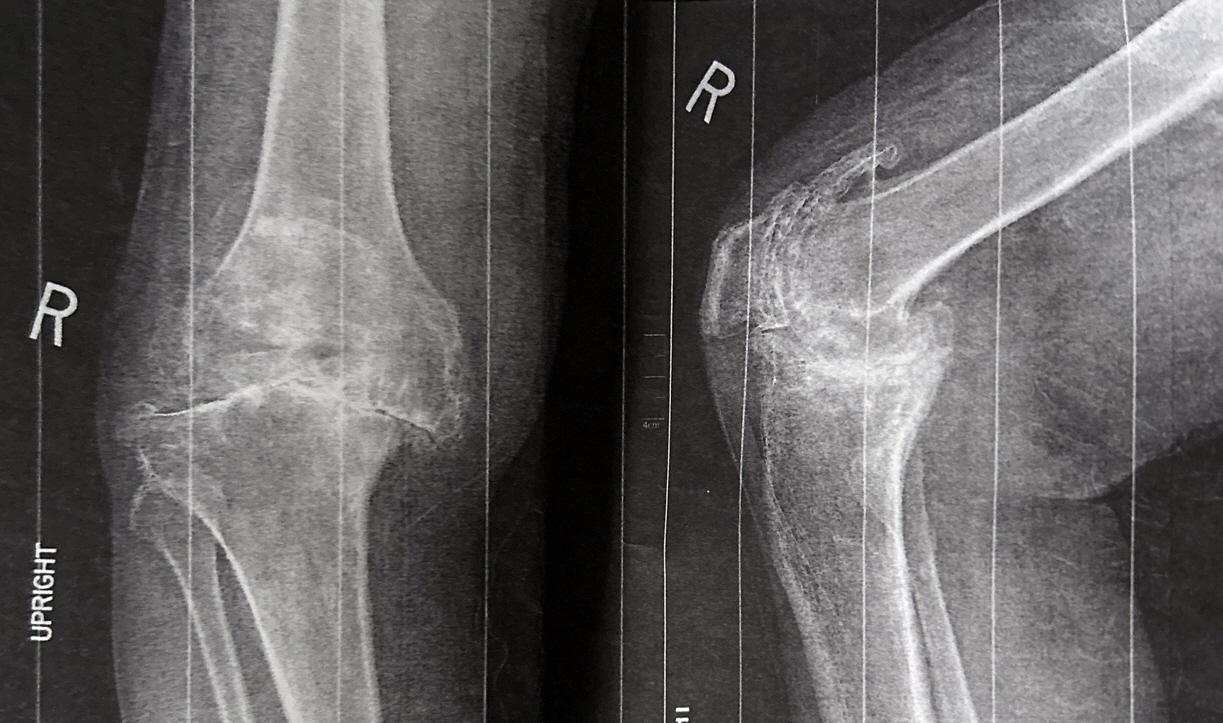

Whether you are a new graduate or an advanced clinician, Pain Series CE will provide an answer and guidance to better understand pain and select the most effective interventions. Pain can no longer be considered merely a symptom. It is currently considered to be a disease. The evaluator’s learning, expertise, or specialty will determine how the evaluator thinks about pain. Soft tissues have long been considered the major source of pain and disability. Soft tissues constitute the site of impairment leading to functional limitation, disability, and pain. The course will focus on the arthroplasty surgical approaches and how they affect the outcome. The course also will provide an explanation of persistent pain following knee arthroplasty.

- Review of functional anatomy and biomechanics of the knee region.

- Review of the most common disorders of the knee region (Iliotibial band Syndrome, Osgood-Schlatter disease, Baker Cyst, and Knee OA)

- Total Knee Arthroplasty TKA, Pre and post-operative rehabilitation, Complications, and Causes of persistent pain and imping after TKA

- Explanation of persistent pain following total knee arthroplasty